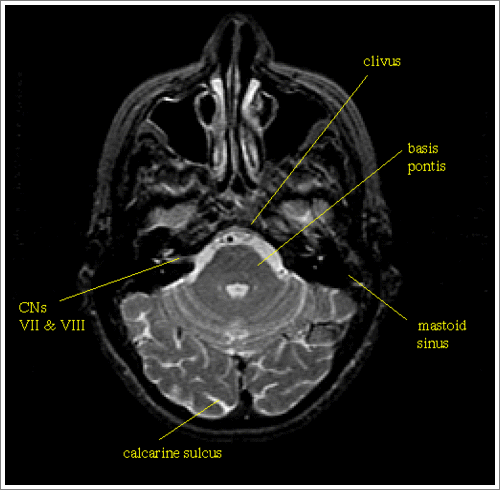

Cranial nerves

[optic nerve]

[optic chiasm]

[trigeminal]

[facial]

[auditory]